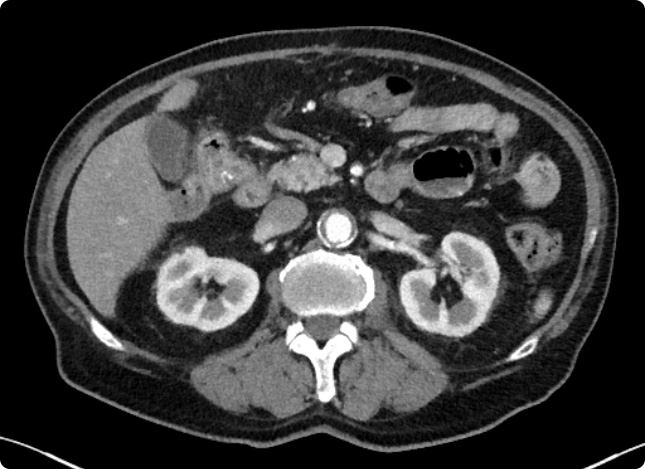

Bei der Computertomographie (CT) werden mit Hilfe von Röntgenstrahlen und modernster Computertechnik Schnittbilder aus verschiedenen Körperabschnitten überlagerungsfrei errechnet. Moderne CTs sind keine Röhren, sondern ähneln einem großen Ring. Je nach Fragestellung dauert eine CT-Untersuchung nur wenige Minuten, der Scan selbst oft nur wenige Sekunden.

Bei vielen Fragestellungen ist es erforderlich, ein jodhaltiges Kontrastmittel über die Armvene zu verabreichen. Das Kontrastmittel „färbt“ Gefäße und Gewebe ein und ermöglicht so eine bessere Bildgebung, um beispielsweise Entzündungen oder Tumore auszuschließen.